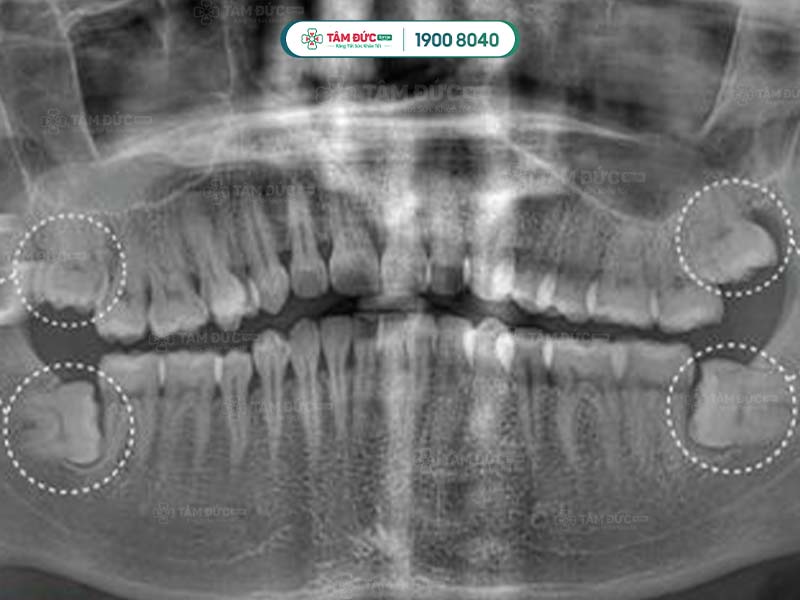

Răng khôn thường mọc ở phía sâu trong khoang miệng, sau răng hàm thứ 2. Răng khôn thường mọc ở 4 vị trí góc miệng: hàm trên trái, hàm trên phải, hàm dưới trái và hàm dưới phải.

Một số ít trường hợp, răng khôn không mọc ở cả 4 vị trí. Có người chỉ mọc 2 chiếc, có người chỉ mọc 1 chiếc. Quý khách không thể tự đếm hay nhìn thấy răng khôn mọc ngầm bằng mắt thường, mà cần phải thông qua chụp phim X-Quang.

Hình dạng của chân răng khôn hay còn gọi là gốc răng khôn ở mỗi người có sự khác biệt. Răng khôn có hình dáng khác với những chiếc răng còn lại, chúng hầu như có từ 2, 3 thậm chí là 4 gốc răng. Các chân này thường hợp nhất với nhau tạo thành chân lớn. Tuy nhiên, một số khác lại cuộn tròn hoặc xòe ra các hướng khác nhau.

Một số trường hợp đặc biệt, răng khôn có thể có nhiều hơn 4 chân răng. Chính vì thế, việc biết được răng khôn có mấy chân là điều cần thiết giúp bác sĩ lựa chọn giải pháp nhổ răng khôn an toàn nhất.

Sau khi nhận kết quả chụp phim, bác sĩ tiến hành đánh giá tình trạng và độ khó của phẫu thuật. Tiếp đến, Quý khách sẽ được tiêm thuốc gây tê tại chỗ. Với trường hợp răng khôn dễ nhổ: bác sĩ tiến hành rạch trên nướu, làm sạch vùng phẫu thuật để tiếp cận và nhổ bỏ răng khôn. Trường hợp khó hơn: răng khôn có nhiều chân thì cuộc phẫu thuật có thể kéo dài. Lúc này bác sĩ sẽ rạch và cắt từng chân của răng khôn để đảm bảo an toàn.